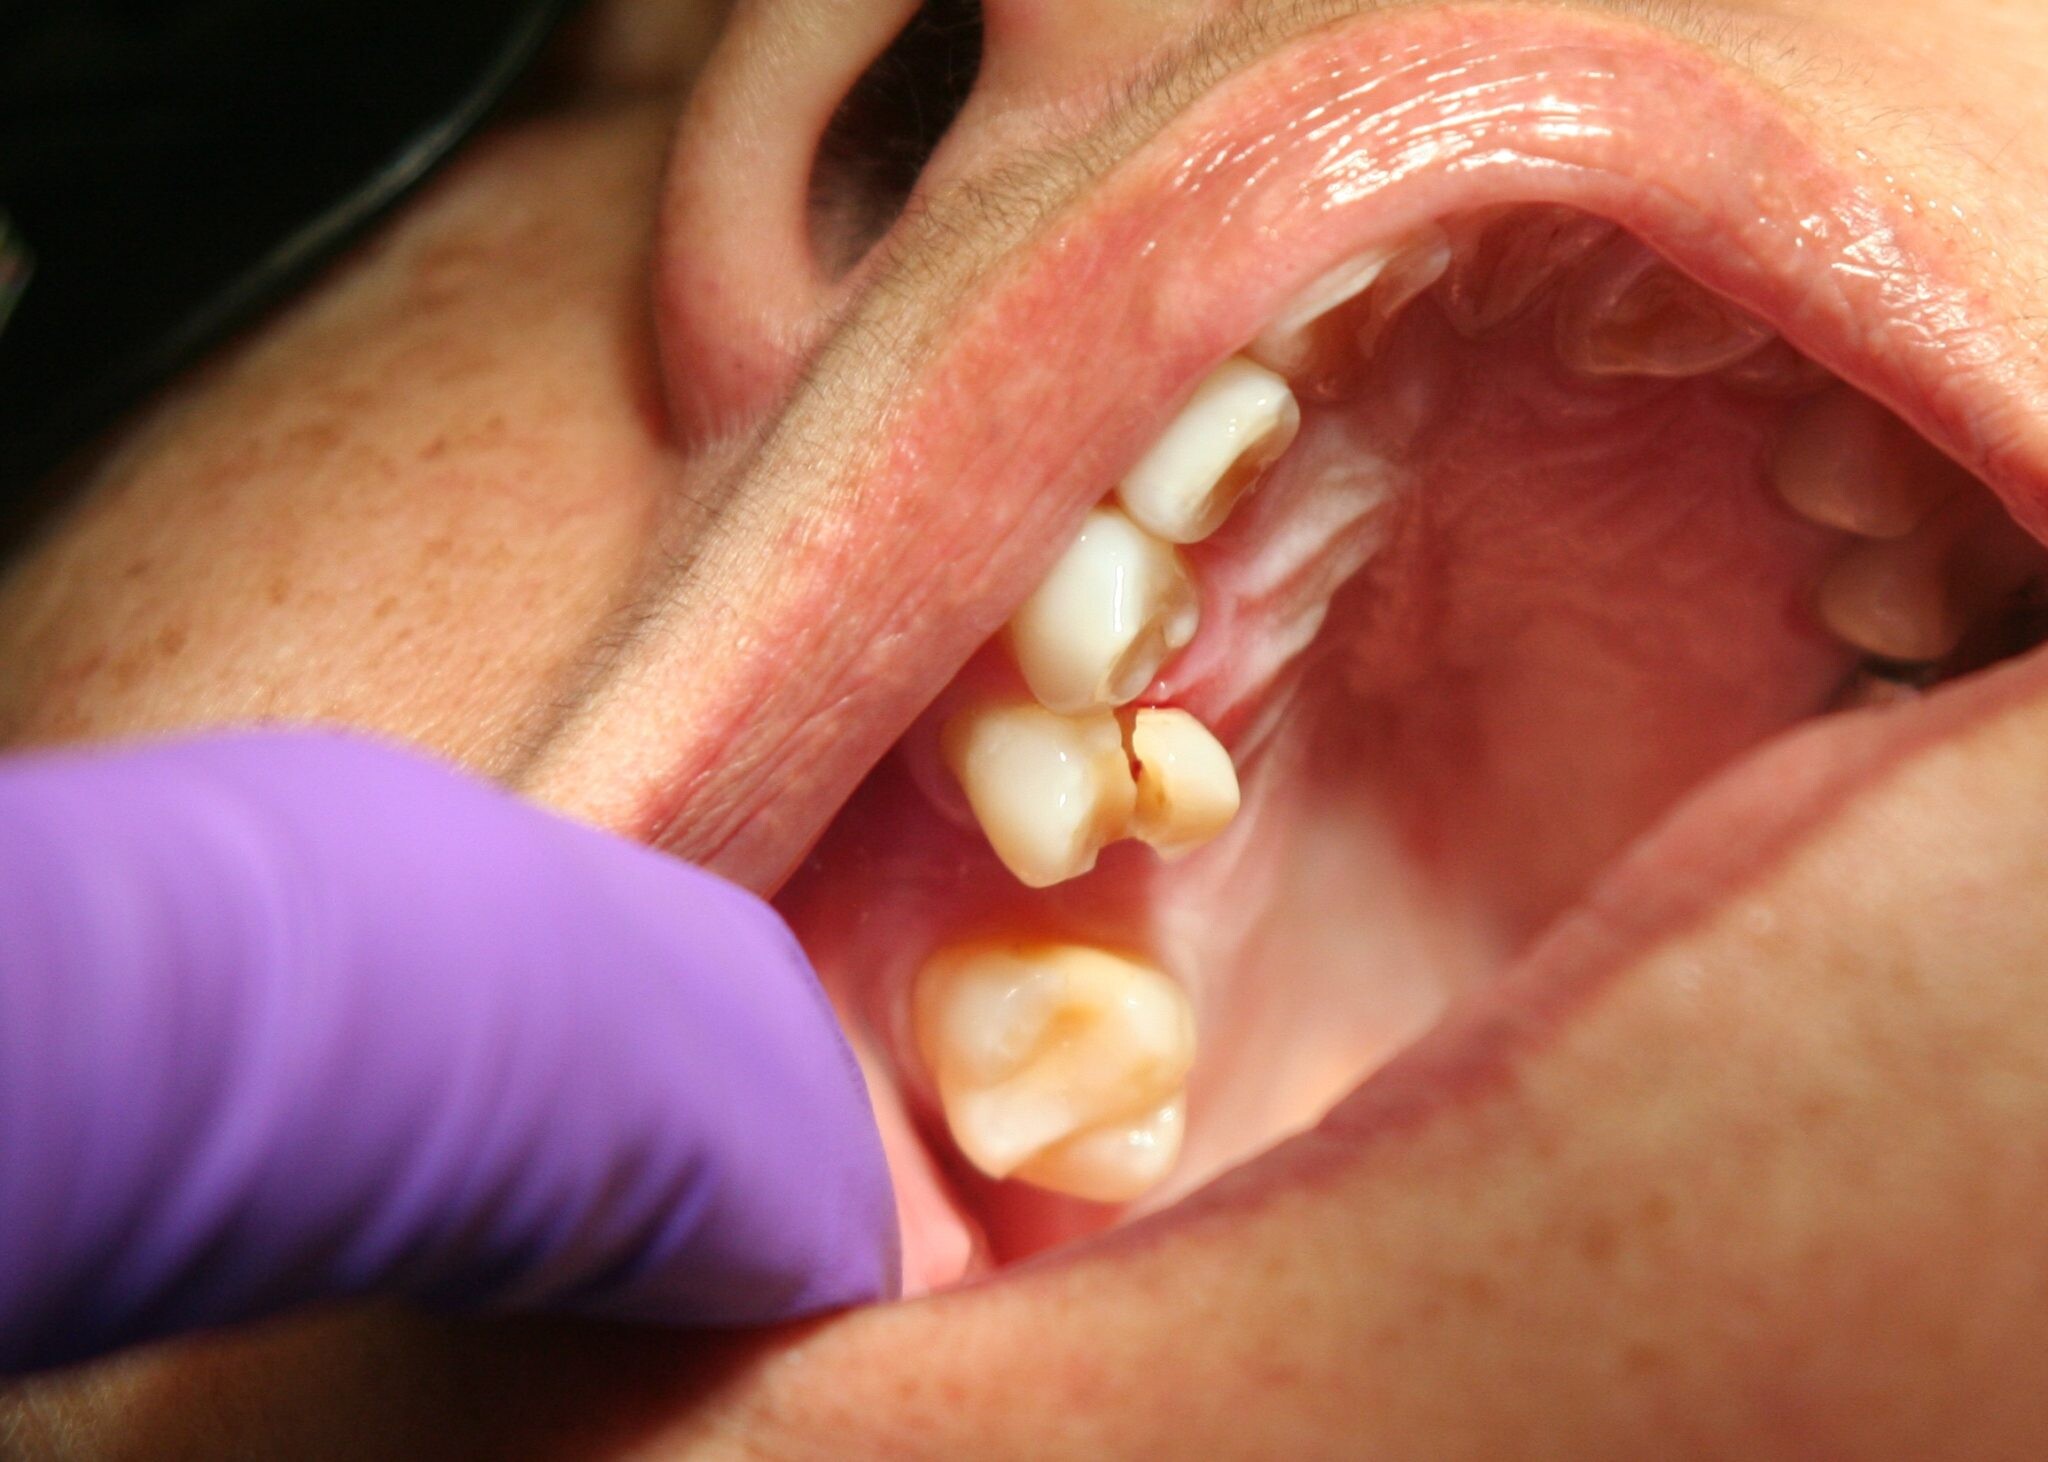

Mutilates the Neighbouring Teeth

Since there is not enough room for the tooth to grow, it will case the teeth to grow in an abnormal manner. This results in impaction of the teeth, giving rise to many other oral problems. When the wisdom tooth emerges against the second set of molar, it might damage them, increasing the risk of acute infection. It will also have an effect on other teeth, which will intensify the need for an orthodontic treatment to align the other teeth.

Tooth Decay

The fully impacted or the partially impacted wisdom teeth are at greater risk of tooth decay, than other teeth. This usually happens, because of the location of the wisdom tooth, especially towards the back of the mouth, which is hard to clean. Moreover, since it lies at the back of the mouth, there are chances of food getting easily trapped between the gums and the tooth, promoting the growth of bacteria.